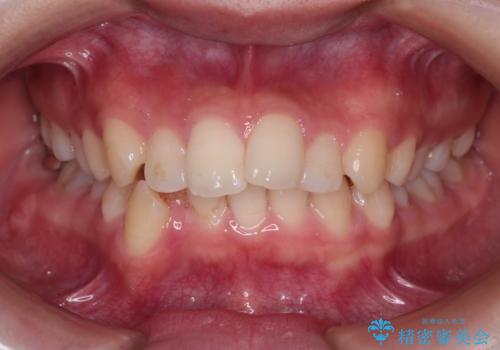

前歯の突出を防ぎながらガタつきを解消。上下左右4番抜歯による審美ワイヤー矯正